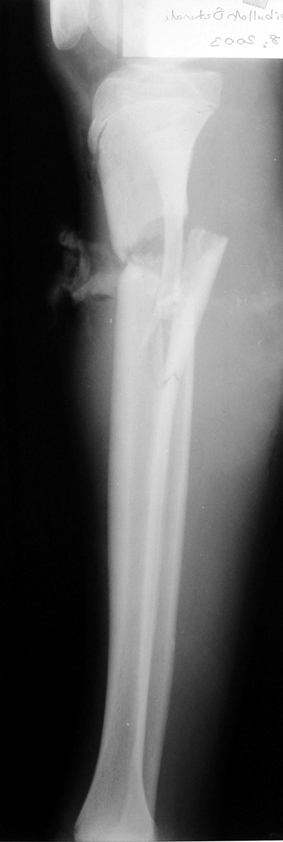

Pseudarthrosis of fracture and pseudarthrosis treatment is currently important problem for orthopedic surgery. Various treatment modalities have been described for pseudarthrosis treatment. All of the treatment methods include high complication rates and additional problems. Leg-length discrepancy, deformity and soft-tissue loss and chronic infection can concomitance with pseudarthrosis. Many internal or external fixation techniques have been described for pseudarthrosis.

Debridement and resection of bone fragment from the pseudarhtosis area vascularized or nonvascularized fibula graft, vascularized muscle flaps, bone grafting followed internal fixation techniques make a option for treatment of pseudarthrosis treatment. But these treatment modalities may not correct deformity and leg-length discrepancy.

Case 2